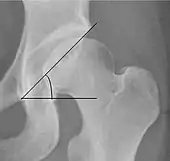

| Sharp angle | ![]() |

Acetabular slope | <45°